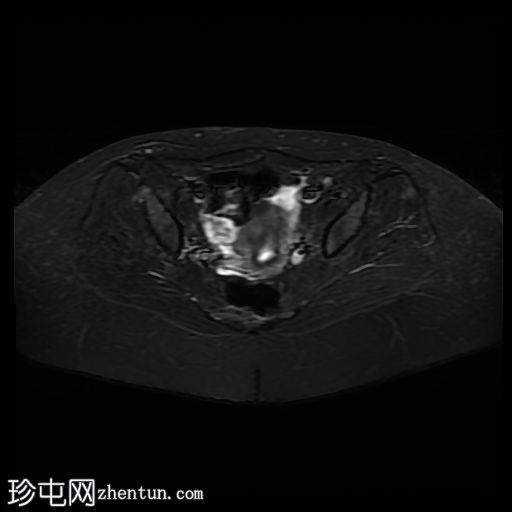

轴位

STIR

偶然发现子宫纵隔,子宫角间夹角为51度,纵隔长度为19mm。

子宫底部可见少量壁内及浆膜下肌瘤。